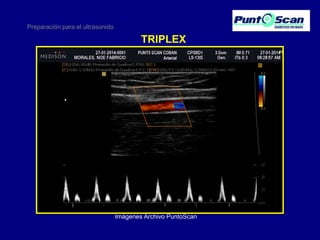

Preparación para el ultrasonido

TRIPLEX

Imágenes Archivo PuntoScan

• 13.

Preparación para elultrasonido TRIPLEX Imágenes Archivo PuntoScan